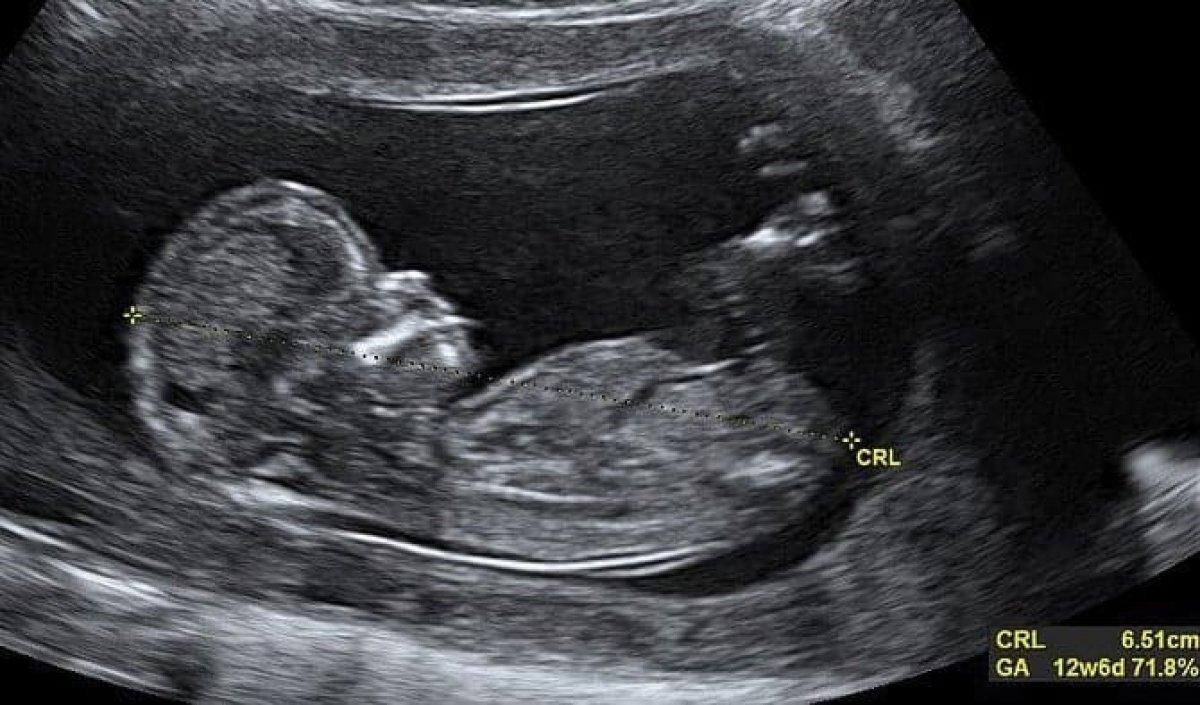

Ebeveynlerin heyecanla beklediği ultrason kontrolünün ardından en çok merak edilen "CRL" değeri nedir...

Anne adaylarının gebelik takipleri esnasına en sık gördükleri ultrason terimlerinden biri de CRL olarak karşımıza çıkıyor.

Peki ultrasonda CRL değeri ne anlama gelir? Sizler için anlattık...

ULTRASONDA CRL NE DEMEK?

Crown Rump Length’ın kısaltması olan CRL, bebeğinizin anne karnında popo ve baş arasındaki mesafesi anlamına gelir. Hata payının en az olduğu ölçüm olarak bilinir.

Özellikle hamileliğin 7-13. haftaları arasında ölçüm yapılır. Son adet döneminde hesaplanan gebelik haftası ile karşılaştırılır ve doğrulaması yapılır. Gebelik dönemizin şüpheli ise yani bebeğinizde gelişme geriliği var ise bu ölçümle belirlenir.